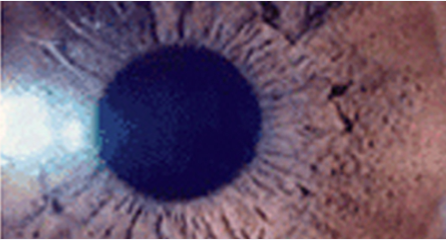

• 수술 후 각막이 얇아져 눈 속의 압력을 견디지 못하고 각막의 중앙 혹은 중앙 아래부위가 불룩하게 앞쪽으로 튀어나오는 현상을 말합니다.

각막은 외부의 압력과 눈 속의 압력을 서로 견디는 견고한 구조물입니다. 라식, 라섹 수술로 인해 각막이 얇아지게 되면 이러한 견고함이 일부 저하되어 원추각막 이라는 합병증이 발생할 수 있습니다. 미국 FDA 안전기준에 준수한 잔여각막두께는 250µm이라고 정해두고 있지만 비교적 안전한 이러한 잔여각막두께에서도 합병증은 보고된 바가 있습니다.

그러므로 미국 FDA 안전기준보다 더 안전한 기준 300µm이상(각막절편두께제외)을 규정하여 수술을 진행하고 있으며, 이 기준에 벗어나는 경우에는 라식, 라섹수술을 시행하지 않고 있습니다.